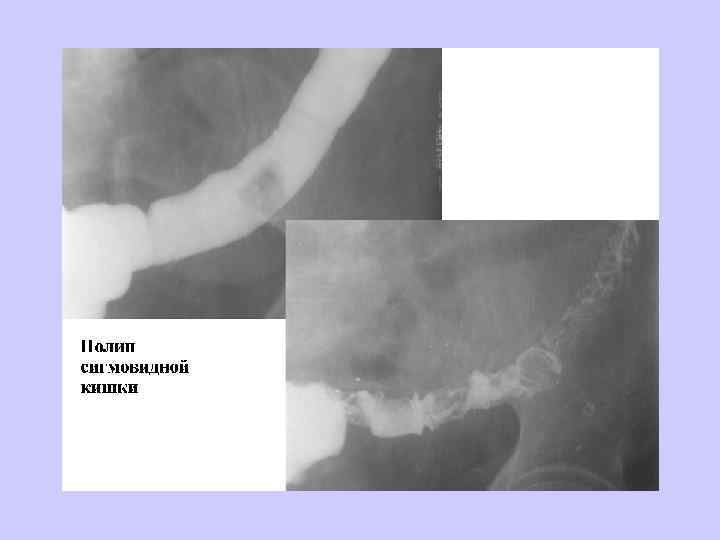

ДИАГНОСТИЧЕСКИЙ АЛГОРИТМ • • • Пальцевое исследование прямой кишки Ректосигмоидоскопия Ирригоскопия Колоноскопия Гистологическое исследование